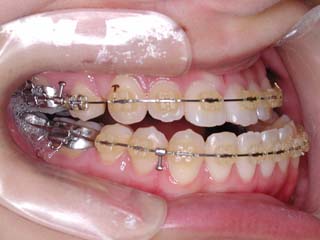

主訴:顎が歪んでいる 下顎が出ている

診断名:骨格性下顎左方偏位を伴う骨格性下顎前突

年齢:28歳

使用した主な装置名:TPB、マルチブラケット装置

抜歯/非抜歯および抜歯部位:抜歯(上顎左右第一小臼歯)

治療期間:動的処置2年3か月、経過観察3年

費用の目安:保険適応 自己負担金として30~50万

リスク、副作用:外科手術によるリスク、マルチブラケット治療に伴う歯根吸収など偶発症が発生するリスクがある。

強い下顎前突と下顎の左方変位がみられます。成長を終了した永久歯列ですので、骨の大きさのズレへのアプローチは大きく別れる所です。程度が小さければ、歯の傾きで補うように解決しますし、大きなズレであれば、外科的に骨のズレを改善する治療が選択されます。前後のズレ、左右のズレと条件が重なってきた場合、より外科矯正での改善が望ましいものとなるでしょう。

一般的な外科矯正治療の流れは、術前矯正・外科矯正・術後矯正・保定治療と移行します。術前矯正では、手術を行う時点で、上下がぴったり合うような歯列に仕上げる事になりますので、逆に言えば、手術をしていない直前においては、とんでもなく噛めない状態となっている事が多いです。このケースでは下顎のみのセットバック(後退術)をSSROにて行いました。